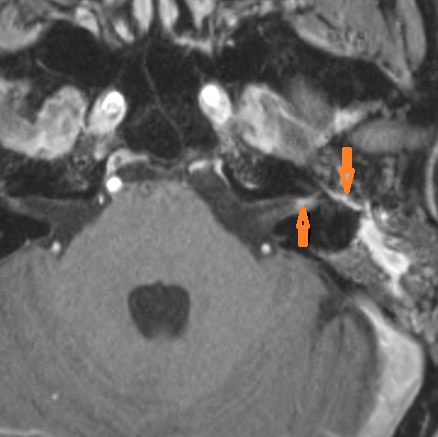

There is evidence of thrombosis, thrombophlebitis or other occlusive or inflammatory process of the sigmoid sinus, transverse sinus, the vein of Labbe’ or jugular bulb. [Yes/No]

There is evidence of thrombosis, thrombophlebitis or other occlusive or inflammatory process of jugular vein. [Yes/No]

There is dural reactive change along the floor of the middle cranial fossa or along the inner surfaces of the petrous portion of the temporal bone. [Yes/No]

There is a subperiosteal, subdural or epidural abscess along the floor of the middle cranial fossa or along the inner surfaces of the petrous portion of the temporal bone. [Yes/No]